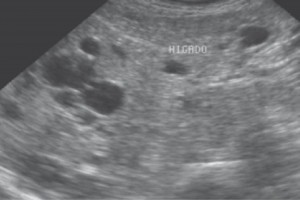

Diplomados en Ultrasonografía